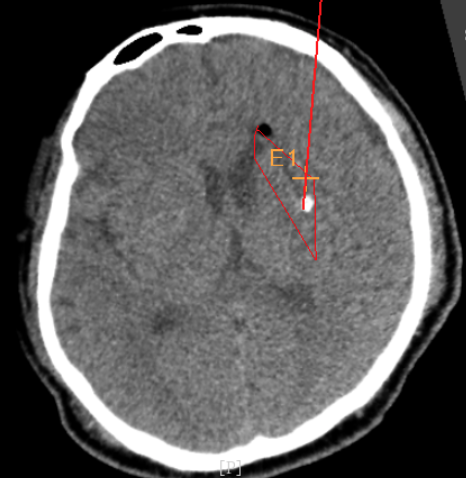

術(shù)前韓帥醫(yī)生使用“睿米”制定手術(shù)規(guī)劃

手術(shù)規(guī)劃在機器人軟件上制定完成